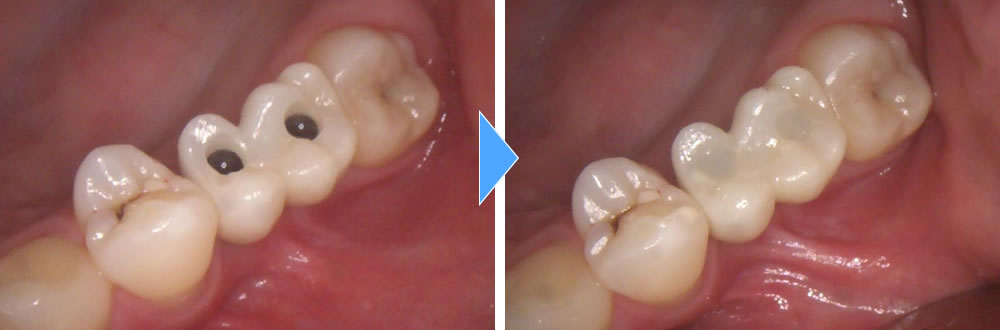

上部構造の装着・治療完了

術後は元々あった歯と同じようにしっかりと噛むことができるようになり、審美的にも機能的にも大変満足していただいております。